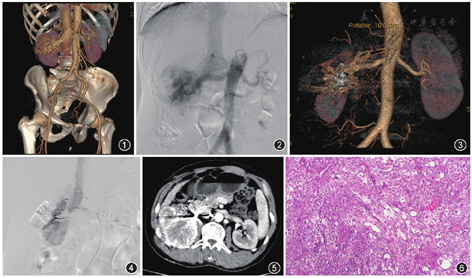

男,47岁,因胸闷、右侧腰痛10 d余于2017年2月24日入我院泌尿外科。外院超声提示:左心房、左心室扩大,二尖瓣、主动脉瓣关闭不全,左心室收缩功能不全,右肾内异常回声(考虑动静脉瘘)。入院诊断:高血压病;心脏扩大,心功能Ⅲ级;右肾动静脉瘘(renal arteriovenous fistula,RAVF)。入院CTA:右RAVF,肾周多发迂曲小血管(图1)。实验室检查:尿常规隐血强阳性,尿红细胞175个/μl,余结果正常。患者入我科于3月7日行介入治疗,术中行右肾动脉造影见右肾多支增粗的供养动脉及大片紊乱的动静脉畸形及明显的动静脉瘘,右肾静脉及下腔静脉快速显影(图2),与术前CTA表现符合。右侧腰2、腰3动脉造影,显示参与右肾异常供血,分别超选至病变血管内,应用350~560、560~710 μm聚乙烯醇(polyvinyl alcohol,PVA;杭州艾力康医药科技有限公司)颗粒栓塞至血流阻断,应用6 mm×14 cm、3 mm×3 cm弹簧圈(Cook,美国)巩固栓塞畸形血管团,造影未见异常血管显影,右肾下极血管正常给予保留。术后患者胸闷、腰痛症状消失,恢复良好出院。于2017年5月16日再次因腰痛就诊,疼痛症状同前,行肾动脉CTA检查,仍考虑为右RAVF(图3),未入院治疗。于2017年8月23日再次入院,行右肾动脉造影,仍可见大片状畸形血管显影及动静脉瘘形成(图4),保留的右肾下极血管也参与异常供血,右侧腰1~腰3动脉参与右肾异常供血,行右肾动脉需完全栓塞术。术中用350~560 μm PVA及6 mm×14 cm、3 mm×3 cm弹簧圈栓塞右肾动脉及参与供血的右侧腰动脉。术后腰痛症状再次缓解并康复出院。患者于2017年10月10日因右侧腰部胀痛第3次入院,行双肾CT检查,因介入治疗后金属伪影影响,病变显示不清(图5)。双肾肾动态显像提示:左肾肾小球滤过率(glomerular filtration rate,GFR)57.19 ml/min,右肾GFR 21.72 ml/min。经泌尿外科会诊,建议行右肾切除术。术中见右肾与周围组织粘连严重、质脆,行右肾切除。切除肾脏病理显示细胞增生活跃伴坏死及细胞变异,诊断肾恶性肾脏血管周上皮样细胞肿瘤(perivascular epithelioid cell tumor,PEComa;图6)。术后2个月,复查CT提示肿瘤复发,后给予肿瘤内科治疗。

肿瘤是引起RAVF的原因之一[1],但肿瘤在影像上具有占位效应及动脉期强化、静脉期强化减低等表现,彩色超声、CT、MRI等诊断肾脏肿瘤并不困难[2,3]。以多支RAVF为主要表现而无明显肿块的肾脏肿瘤诊断较困难,相关文献报道较少。本例患者影像检查无肿瘤表现,患者有高血压、心脏改变等RAVF引起的症状。因此,本病例最初即被误诊为RAVF。超选择肾动脉栓塞是公认的治疗RAVF的最佳方法[4],PVA颗粒、弹簧圈也是公认的永久栓塞剂。但本例患者经2次栓塞治疗后再次复发,说明病变并非动静脉瘘单一因素所致,最终病理证实为恶性肾PEComa。